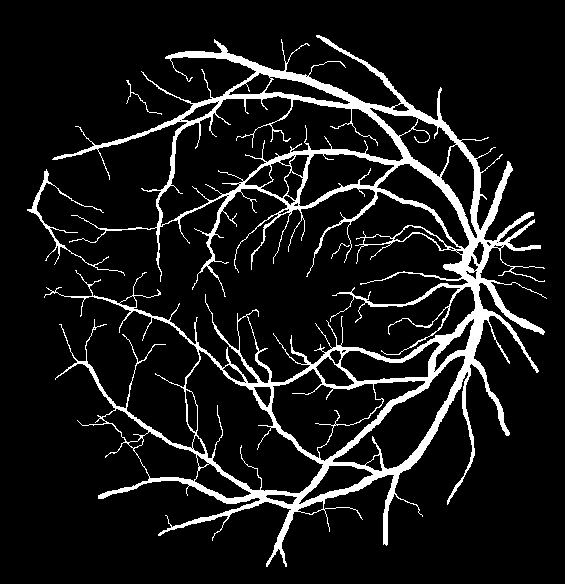

Refer to caption

(a) Ground truth binary mask

(b) Thick vessels binary mask

(c) Thin vessels binary mask

Figure 4: Segregation of ground truth of sample DRIVE image.

After Level-I balancing, the network model is still biased towards the prediction of thick vessel pixels, leaving many thin vessel pixels unidentified. This is because the number of thick vessel’s pixels exceeds those of thin vessel’s pixels. Thus, there is a need to create a balance between the distribution of thick and thin vessel pixels in the training set, termed intra-class balancing. This can be considered another level of balancing on top of Level-I balancing, hence the term Level-II balancing. The balancing obtained from Level-I is further refined by giving an equivalent representation to thick vessel pixels and thin vessel pixels in the training set. The categorization of thick and thin vessel patches requires the segregation of ground truth binary images based on thick and thin vessel pixels. The thick vessels pixels mask is acquired through morphological opening [44] operation, while the thin vessels pixels mask is obtained by subtracting the thick vessel mask from the original ground truth mask. Figure 4 shows the ground truth image of a sample DRIVE image along with the corresponding thick and thin vessel mask images.